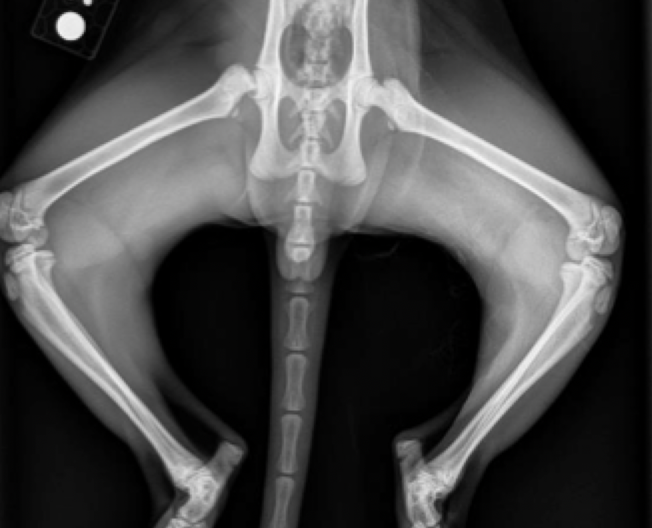

Rt. Femoral Capital Physeal Fracture

muscle atrophy evident on the Rt. leg

Salter harris type 1

delayed physeal closure in early neutered male

Femoral Capital physeal fracture